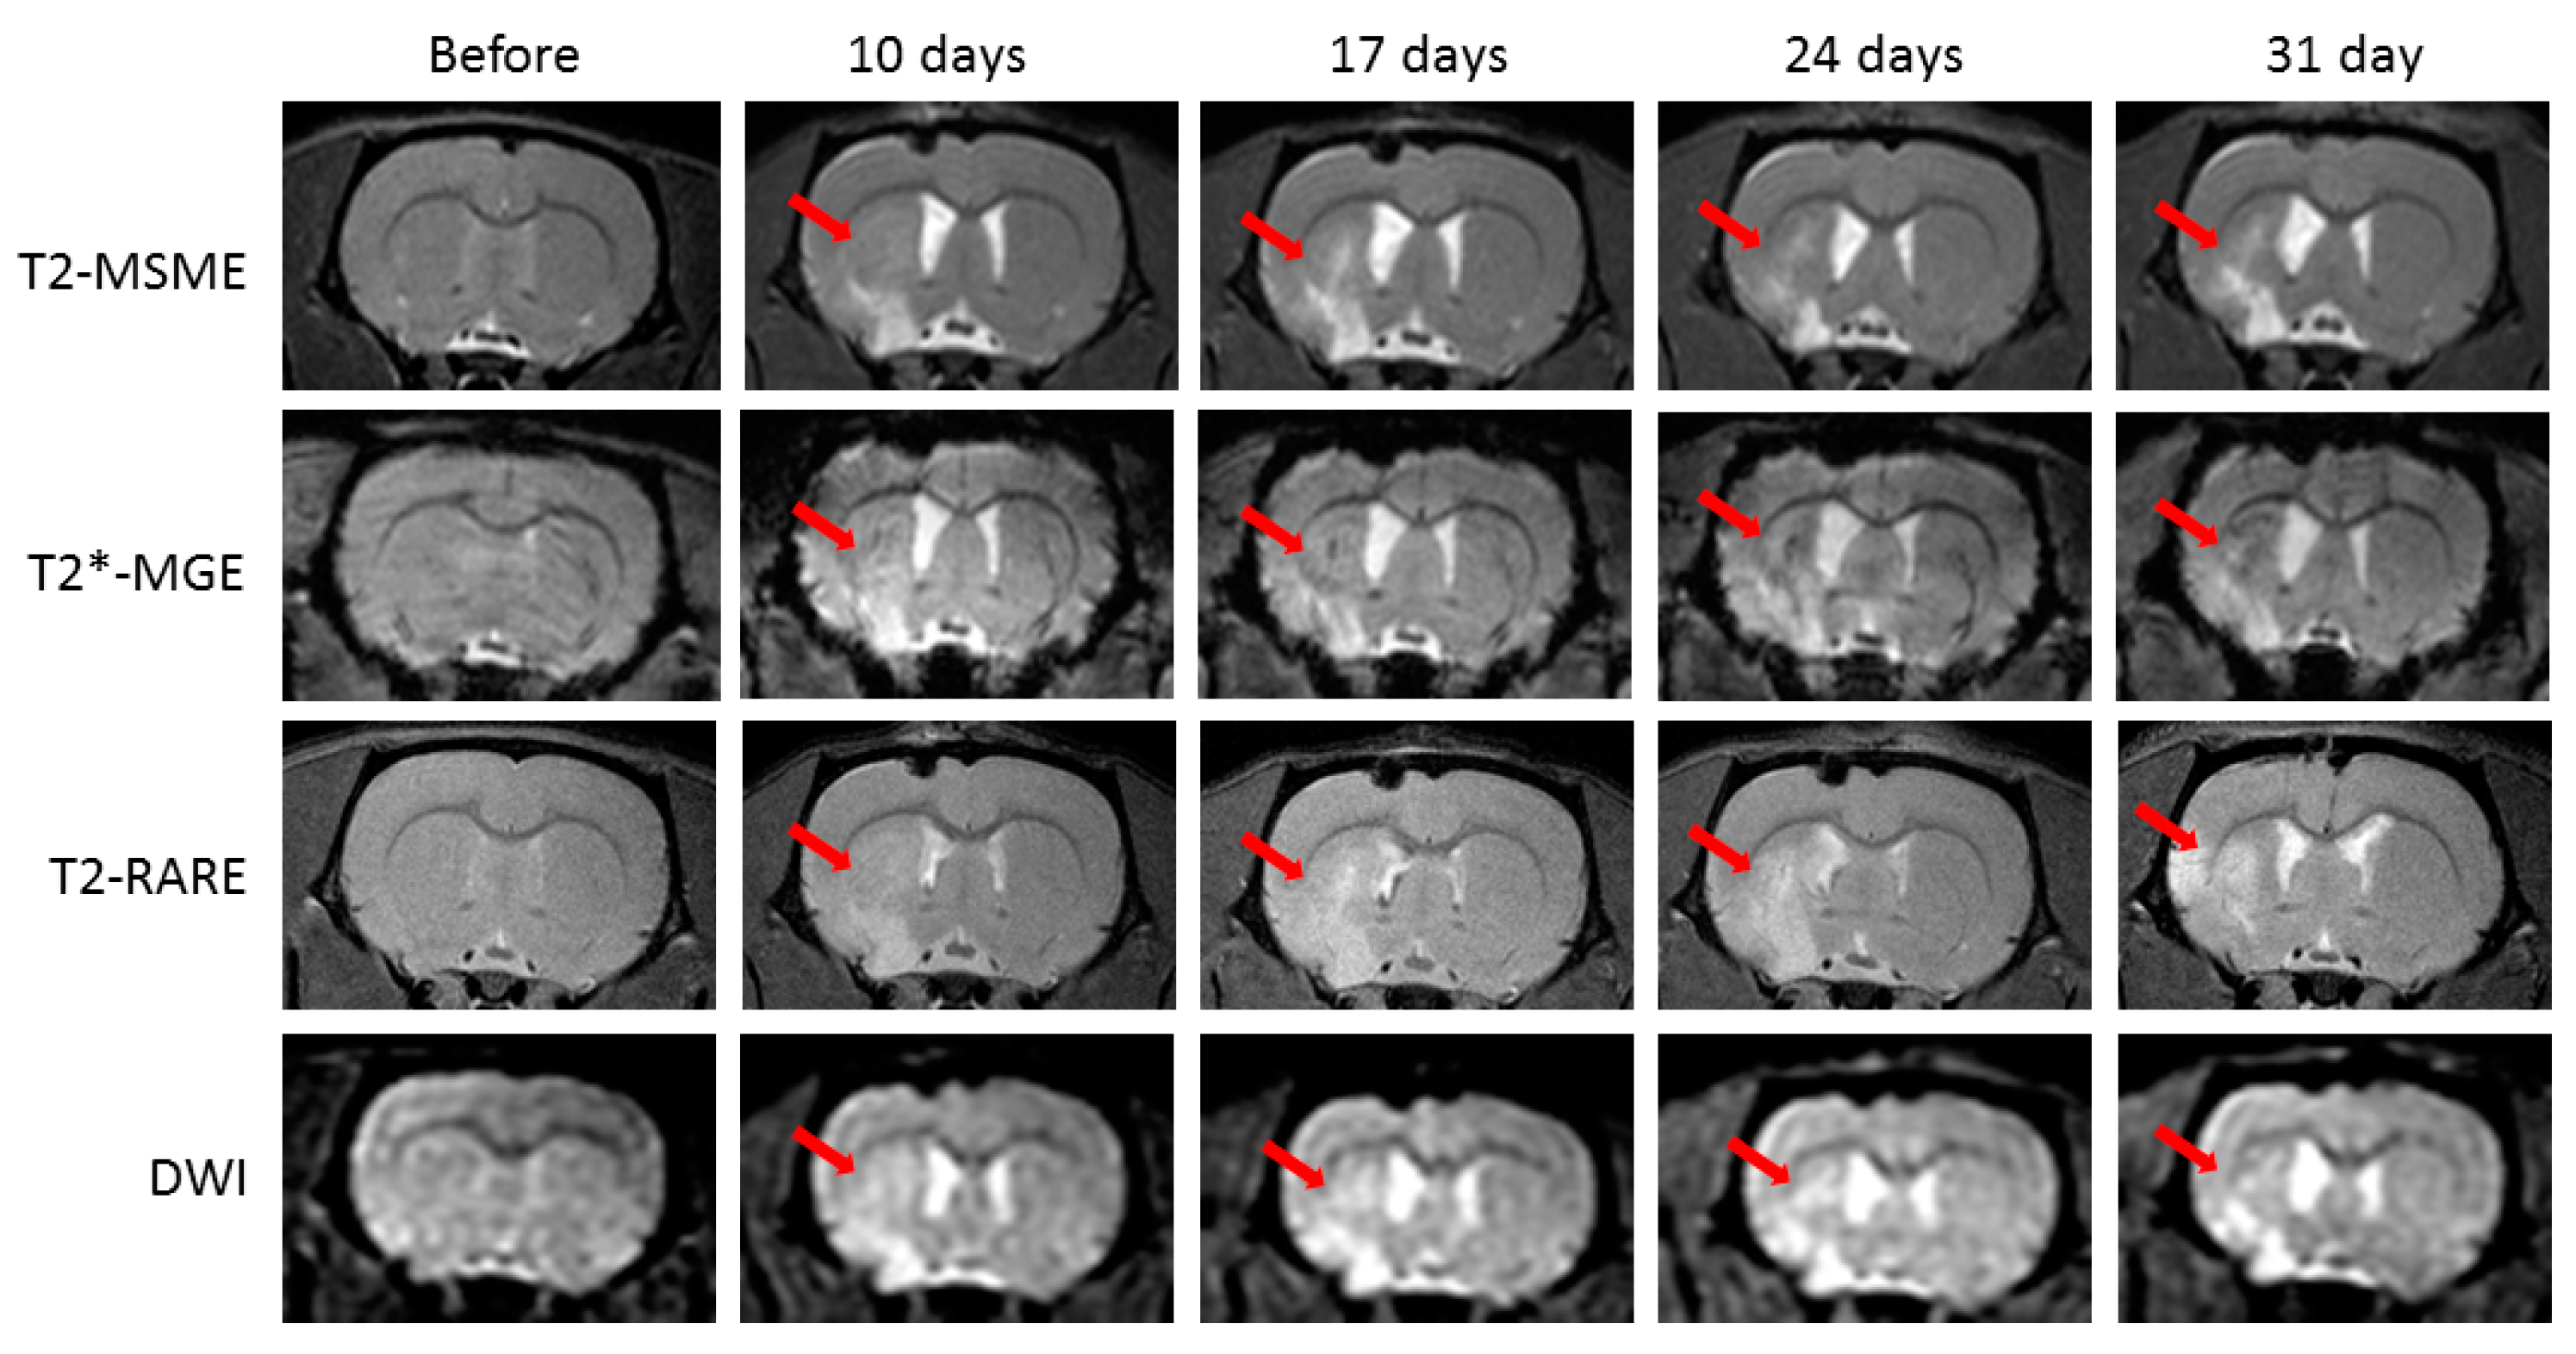

2.1. Neurological Deficit and Time Course of Ischemic Lesions

- (1)

- T2-weighted multislice multiecho (T2-MSME): TR = 2700 ms, TE = 7.3ms, FOV = 36 × 36 mm, image resolution 0.2 × 0.2 mm2, slice thickness 1 mm, matrix 180 × 180, 1 signal average, scan time 6 min 24 s.

- (2)

- T2-weighted turbo rapid acquisition with relaxation enhancement (T2 TURBO RARE): TR = 2 s, TE = 7.6 ms, FOV = 36 × 36 mm, image resolution 0.12 × 0.12 mm2, slice thickness 1 mm, matrix 300 × 300, 3 signal averages, turbo factor 4, scan time 7 min 30 s.

- (3)

- T2*-weighted multiple gradient echo (T2*-MGE): number of echoes = 9, first echo TE = 2.718 ms, echo spacing 2.9 ms, TR = 950 ms, flip angle 20 degree, FOV = 36 × 36 mm, slice thickness 1 mm, image resolution 0.2 × 0.2 mm2, matrix 180 × 180, 4 signal averages, scan time 8 min.

- (4)

- Diffusion-weighted imaging (DWI): TR/TE = 3200/19 ms, 120 × 120 matrix, FOV = 36 × 36 mm2, matrix size = 128 × 128, section thickness = 0.9 mm, number of diffusion gradient directions = 6, one signal average, scan time 1 min 4 s.